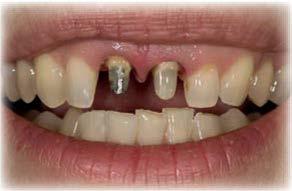

Elevación de seno transcrestal con implantes cortos versus elevación de seno convencional con ventana lateral

Estudio retrospectivo comparativo a boca partida

La rehabilitación del maxilar superior posterior mediante implantes dentales se ha visto condicionada clásicamente por la neumatización excesiva del seno maxilar al perderse los dientes relacionados con el mismo (dientes antrales) (1, 2). En estos casos, se pierde gran parte de la altura del reborde óseo residual generándose atrofias verticales, que pueden limitar, de forma importante, la inserción de implantes de manera directa (3-5).

Esta ocupación del seno de la cresta residual adyacente es diferente en función del diente a extraer, la pérdida ósea asociada a ese diente y la presencia, o no, de comunicación de la potencial infección odontógena con el seno. Aun así, es frecuente que la mayor pérdida en altura derivada del proceso de neumatización del

seno post-extracción sea para el segundo molar o cuando se realiza la extracción del primer y segundo molar simultáneamente (6). Cuando los dientes se han perdido y el seno ha ocupado gran parte del volumen óseo residual de la zona del maxilar superior en su zona posterior, clásicamente, se realizaba una técnica de elevación de seno por abordaje lateral para, mediante un injerto óseo compuesto por diferentes materiales (hueso autólogo, biomaterial o mezcla de ambos generalmente), volver a recuperar la altura de cresta ausente y poder insertar los implantes dentales posteriormente o en el mismo procedimiento, siempre que existiese un volumen óseo residual que permitiese que los implantes quedaran estables (7-9).